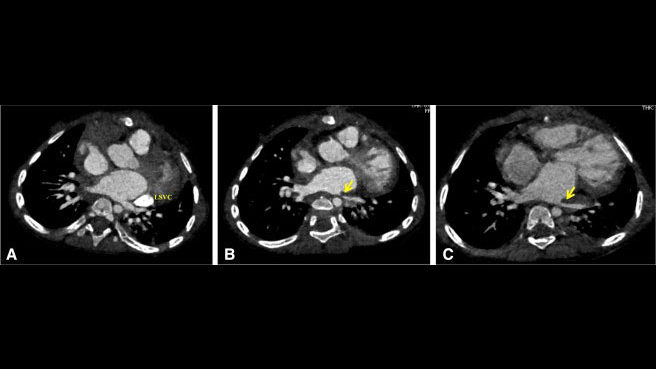

A recent case was reported where a child with complete atrioventricular septal defect (AVSD) developed left lower pulmonary stenosis with secondary pulmonary arterial hypertension (image on the left) following cardiac surgery. The authors described the use of an aortopexy (a technique used to move the ascending aorta anteriorly and fix it further away from the heart and the airways) to relieve pulmonary vein stenosis. The operation seemed to be successful as the pulmonary vein appeared to be larger on repeat chest computed tomography imaging (image on the right) and the pulmonary arterial pressure had decreased at 2 years from surgery. This report is interesting and the operation deserves further consideration in children with pulmonary vein stenosis/obstruction due to anatomic compression of the vein between the anteriorly located ascending aorta and the enlarged heart, particularly as the procedure is much less invasive than direct intervention on the pulmonary vein.